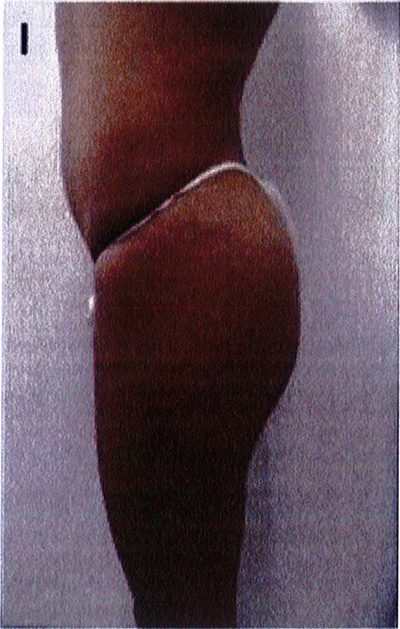

Để tránh tình trạng quá ngắn hoặc quá dài của vùng mông (hay còn gọi là mông dài/ngắn) thì tác giả đã kết hợp một phép đo đơn giản trước phẫu thuật, đo khoảng cách từ mào chậu phía sau tới đường ngang đi qua trung điểm nếp liên mông (khoảng cách A) và từ đường ngang đó tới nếp lằn mông (khoảng cách B) (Hình 1) đế tính vị trí chuẩn xác của khối im- plant.

Để tránh tình trạng phần mông trên được nâng lên quá mức, khoảng cách A thông thường phải gấp đôi khoảng B để có thể phù hợp cho nâng mông dưới cơ.

Nếu khoảng cách A ngắn hơn, nên sử dụng mặt phẳng trong cơ để tạo điều kiện cho khối im- plant được đẩy xuống thấp hơn 1 chút, giúp đạt được kết quả thẩm mỹ lý tưởng.

Hình. 1. Đánh giá trước phẫu thuật để lựa chọn bệnh nhân với mặt phẳng im- plant phù hợp.